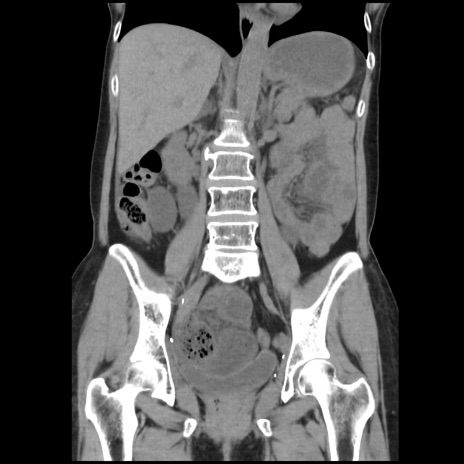

症例32(冠状断像)

【症例】40歳代 女性

【主訴】上腹部痛、嘔気・嘔吐

【現病歴】約9時間前頃から急に上腹部痛、嘔気、嘔吐が出現。改善しないため救急要請。

【既往歴】子宮頚癌(広汎子宮全摘術、放射線療法)、腸閉塞

【身体所見】腹部:平坦、軟、腸雑音亢進、上腹部を中心に腹部全体に圧痛あり。

【データ】WBC 8400、CRP 0.03